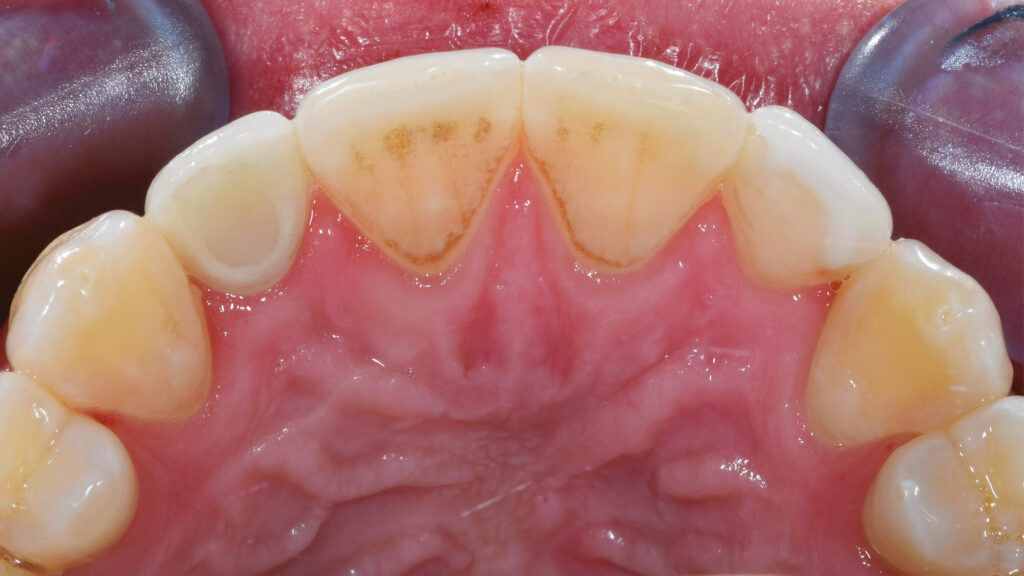

Ein Blick auf die Ausgangssituation (Abb. 1) verdeutlicht die Problematik bei diesem jungen Patienten. Der Milchzahn in regio 12 ist stark verfärbt. Zusätzlich beeinträchtigt der verkleinerte Zahn 22 (Mikrodontie) das ästhetische Bild. Auch der Gingivaverlauf erscheint unharmonisch. Abbildung 2 zeigt die Situation nach kieferorthopädischer Erstbehandlung. Während dieser Behandlungsphase konnte im Frontzahnbereich Platz für das Implantat (TiUltra, Nobel Biocare, Zürich, Schweiz) regio 12 und für das Keramikveneer an Zahn 22 geschaffen werden. Dies bildet die Grundlage für ein natürliches und harmonisches Erscheinungsbild.

Paradigmenwechsel:

Nach der Heilung des Weichgewebes sind die arkadenförmige Kontur der Gingiva und die Papillen deutlich zu erkennen (Abb. 42 und 43). Etwa sechs Monate nach der Osseointegration und Konditionierung der Gingiva wird die Situation mit dem Intraoralscanner erfasst, um mit der Herstellung der implantatprothetischen Versorgung fortzufahren. Nach dem Aufschrauben des Scanbodys auf das Implantat erfolgt der Scanvorgang (Abb. 44). Intraoralscanner gehören zu den aufregendsten neuen Technologien in der Zahnmedizin. Die digitale Abformung bietet dem Patienten deutlich mehr Komfort. Zudem werden klinische Abläufe vereinfacht und die Kommunikation mit dem Zahntechniker verbessert. Im nächsten Schritt werden die STL-Dateien für den Modelldruck aufbereitet (Abb. 45). Vor dem Scannen der gedruckten Modelle muss das Modellanalog regio 12 eingesetzt werden. Das Modell mit abnehmbarer Gingivamaske ist für die Aufnahme des Modellanalogs durch eine Öffnung vorbereitet und besitzt im unteren Bereich des Ausschnittes eine Art Verriegelungsmechanismus (Abb. 46). Dies gewährleistet einen sicheren Presspassung und eine korrekte, automatisch zentrierte Einschubposition (Abb. 47).

Die Gestaltung des marginalen Randes („Präparationsrand”) im bukkalen Bereich erfolgt in Absprache mit dem Zahnarzt ca. 0,2 mm subgingival (Abb. 52). Palatinal endet die Verblendkeramik supragingival, um hier die biologischen Vorteile des Zirkonoxids zu nutzen (Weichgewebekonditionierung) (Abb. 53). Vor allem im Frontzahnbereich wird das individualisierte Emergenzprofil als wichtiger Faktor für die Rekonstruktion einer zufriedenstellenden Ästhetik angesehen. Zudem werden im Frontzahnbereich mit Zirkonoxid biologisch und ästhetisch bessere Ergebnisse erzielt als mit Titan, das bei dünnem Gingiva-Biotyp durchscheinen kann (Abb. 54 und 55).

Die individuelle Formgebung der ASC-Implantatkronen ermöglicht einen reizfreien Schleimhautkontakt mit Titanadapter und konischer Innenverbindung zum Implantat (Abb. 56 und 57). Die keramische Verblendung des Zirkonoxid-Abutments erfolgt analog und ebenso detailgetreu wie beim keramischen Veneer und mit der gleichen Verblendkeramik (Lumex AC). Nach der Verblendung wird die Implantatkrone auf dem Meistermodell verschraubt und eine letzte Kontrolle der Kontaktflächen (Abb. 58 und 59), der Artikulation, der seitlichen Bewegungen und der Eckzahnführung durchgeführt. Abbildung 60 zeigt den nahtlosen Übergang der Implantatkrone zur natürlichen Gingiva. Eine Überkonturierung könnte zu einer apikalen Verschiebung führen. Eine polar_eyes-Aufnahme macht das Innere der Krone und die Details besser sichtbar (Abb. 61).